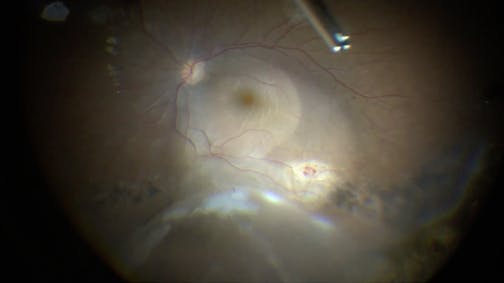

Optic Nerve Pit

Kourous A. Rezaei, MD